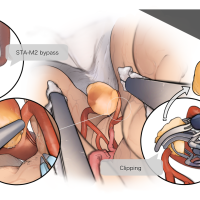

術後イラストシリーズ